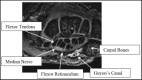

Carpal tunnel syndrome costs the United States billions of dollars each year. The majority of patients are industrial workers, females, and the elderly who first present to their primary care physicians. Therefore, it is essential that the primary care physician understand this syndrome in order to diagnose and direct treatment. Here we present a review of the anatomy, pathophysiology, diagnosis, and current treatment of carpal tunnel syndrome that is relevant for the treating primary care physician. In addition, we discuss the role of the primary care physician in the diagnosis, management, and treatment of carpal tunnel syndrome. The aim of this review is to improve the integrated care of those patients suffering from carpal tunnel syndrome.